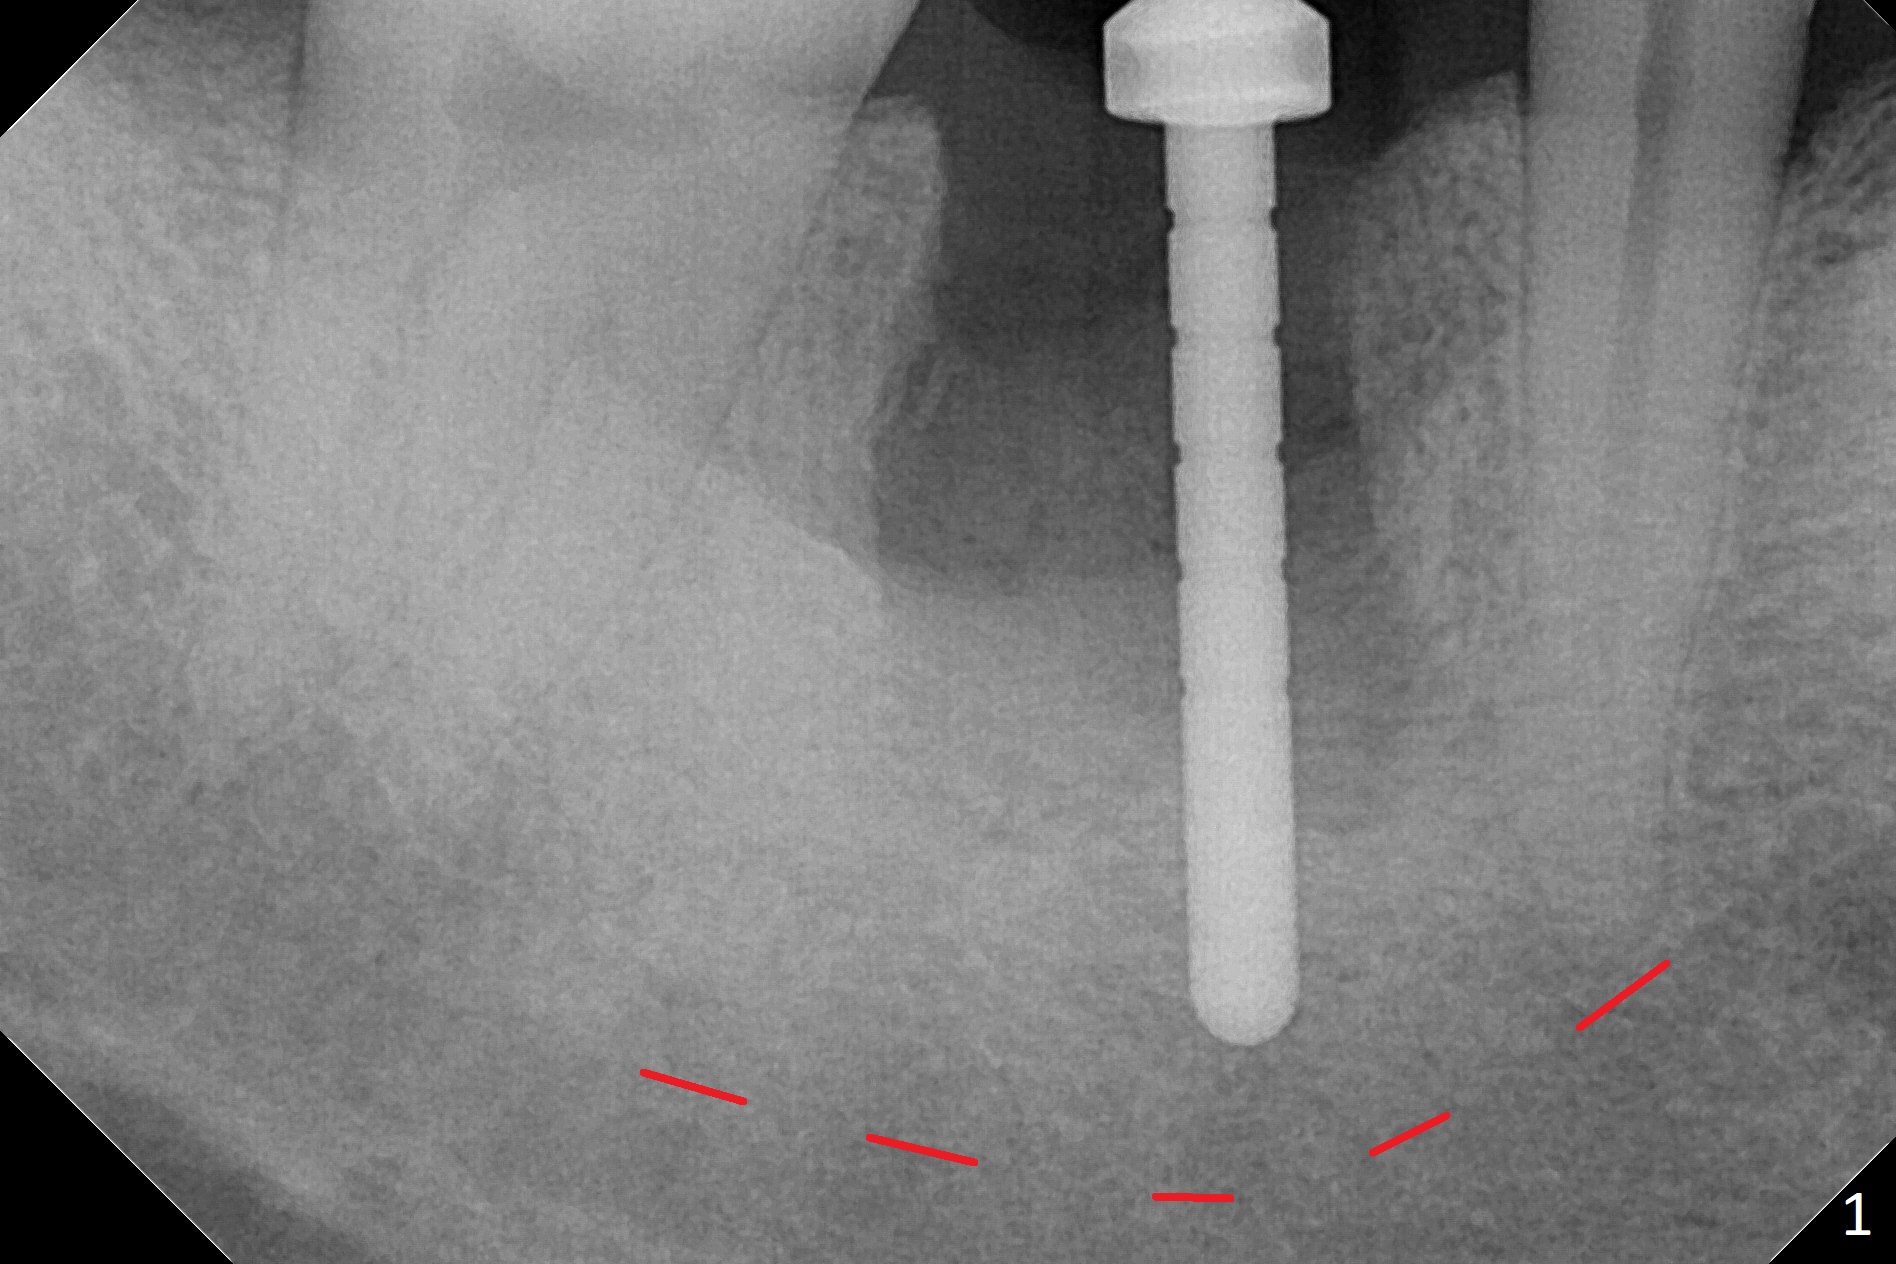

After the tooth #30 is extracted, the socket is 18 mm deep and the lingual plate is 4 mm tall. With hemorrhage, visibility of the socket, especially the bottom, is poor. The septum is almost completely defective. Following removal of the most buccal portion of the septum, osteotomy is initiated as buccal as possible, but it is mesial (Fig.1). In spite of effort to move the osteotomy distal, the osteotomy remains mesial and superficial (Fig.2 with 5 mm tap drill). Pain control is poor with infiltration. It appears that the smaller osteotomy (Fig.2 yellow line) may have extended close to the superior border of the Inferior Alveolar Canal (red line). It appears that there is 8.5 mm bone distal with ~ 2 mm clearance. After mandibular block, a new osteotomy is made distal; when a 3.8 mm drill is being used, there is hemorrhage from the osteotomy with apparent violation of the Canal integrity (Fig.3,4). But hemostasis is achieved with gauze pressure. A 5x13 mm implant is placed superficially (Fig.5) with a trace of the previous osteotomy (yellow line) and deep space created by the mesial osteotomy (*). Apparently the pathological and iatrogenic defects are filled with allograft (Fig.6 *). Guided surgery could have avoided the mesial osteotomy.

Fortunately no paresthesia is reported postop. Why is the Inferior Alveolar Canal not violated? Fig.7 is a coronal section of CBCT taken for a 40-year-old man at the lower 1st molar (at the septum). At the region, the Canal (brown circle) is close to the lingual plate (L). Because of severe bone loss of the lingual plate of this case (Fig.8 *), osteotomy is intentionally created buccal (green). The deep osteotomy may not contact the Canal, while the hemorrhage may stem from the medullary space (M in Fig.4,7). Bone morphology at the coronal end of the implant apparently changes 4 months postop, suggesting osteointegration (Fig.9). Impression is taken. Bone density around the implant at the crest seems to increase (Fig.10), while there is no soft tissue deficiency 10 months post cementation (Fig.11). The bone appears to regenerate toward the abutment, particularly distally, 14.5 months post cementation (Fig.12). Periimplantitis develops (bleeding on water pik and erythematous and tender buccal gingiva) 1 year 7 months post cementation (Fig.13,14). The 1st three threads are exposed (*). Bone graft with PRF and 6-month membrane or Cytoplast will be needed. Pain disappears 3 days of oral antibiotic. The gingiva looks healthy 1 month later when he returns for bone graft (Fig.15). But the lingual gingival cuff is not so healthy when the crown/abutment is removed (Fig.16 <). Bone graft is not done. For those patients with suboptimal oral hygiene, implants should be placed as low as possible, better with guide for precision.